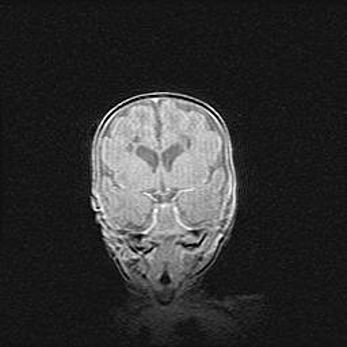

Неполная лизэнцефалия (пахигирия). Открытая гидроцефалия.

Возраст: 17 дней

Вес: 3110 г

Пол: мужской

Окружность головы: 33,5 см

Срок гестации: 35-36 недель

Лизэнцефалия—недоразвитие корковой пластинки и мозговых извилин в результате нарушения миграции нейронов коры. Поверхность мозговых полушарий гладкая. Микроскопически выявляется отсутствие нормальных слоев коры и скопление групп нейронов в подкорковом белом веществе.

Пахигирия—уменьшение числа вторичных извилин. В пораженном полушарии нервные клетки образуют толстый недифференцированный слой с неправильно расположенными нервными волокнами и группами гетеротопных клеток. Нервные клетки незрелые. Белое вещество истончено. При этом нередко аномально развит корково-спинномозговой путь.